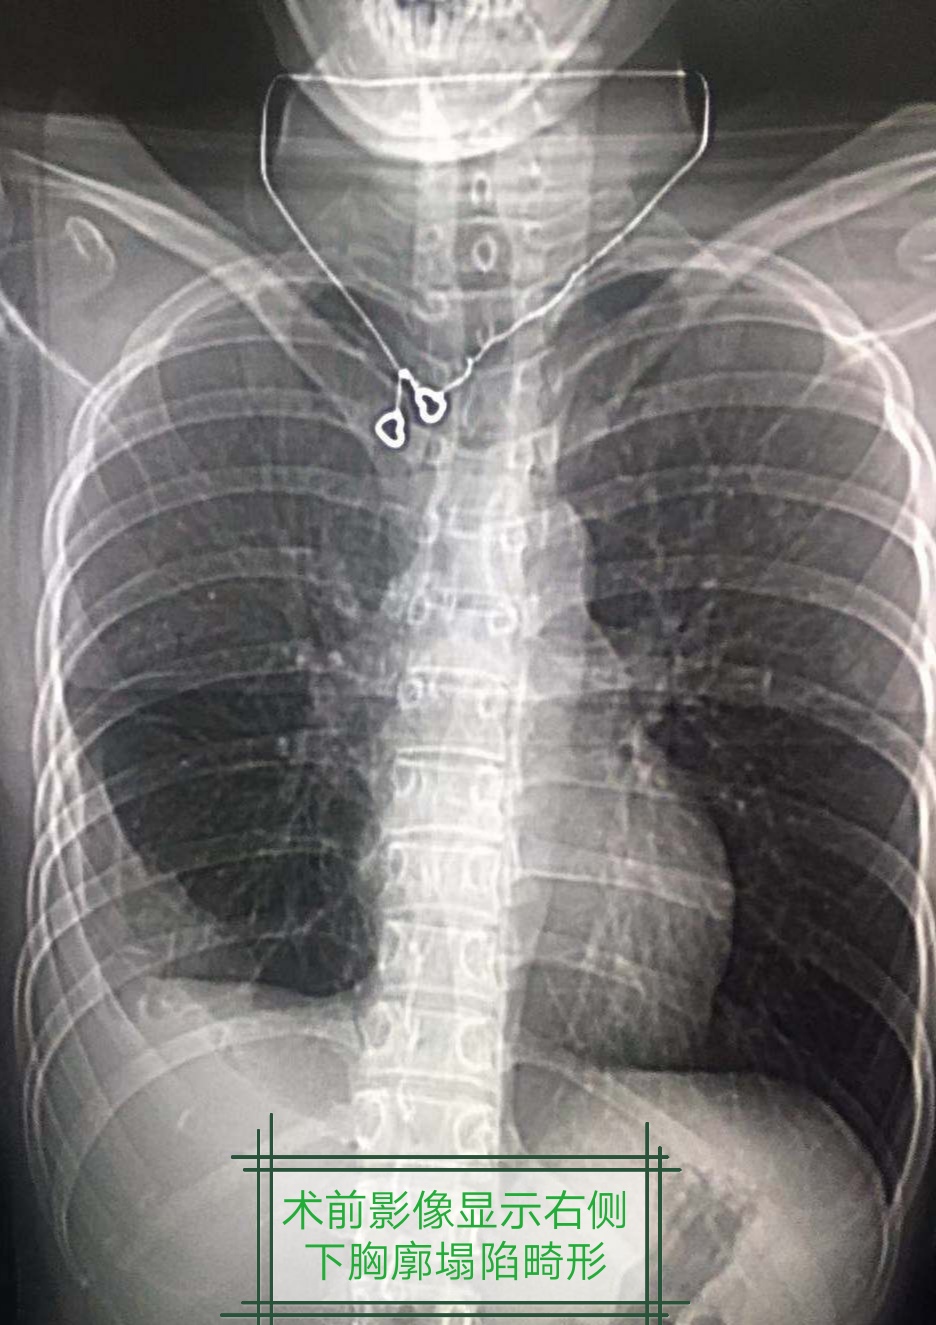

一位花季女孩不幸遭受慢性脓*摧胸**残,保守治疗右侧脓腔不能消灭,胸廓塌陷,开胸手术实在难以接受������

邻市的同道了解我们开展的完全胸腔镜手术治疗慢性脓胸技术特色,向病人力荐。病人欣然自费过来手术,这样的信任,我们怎能不倾力而为哪!甚至病人手术全麻不想安放导尿管的要求,我们也尽力满足,不为别的,只为其生命相托!